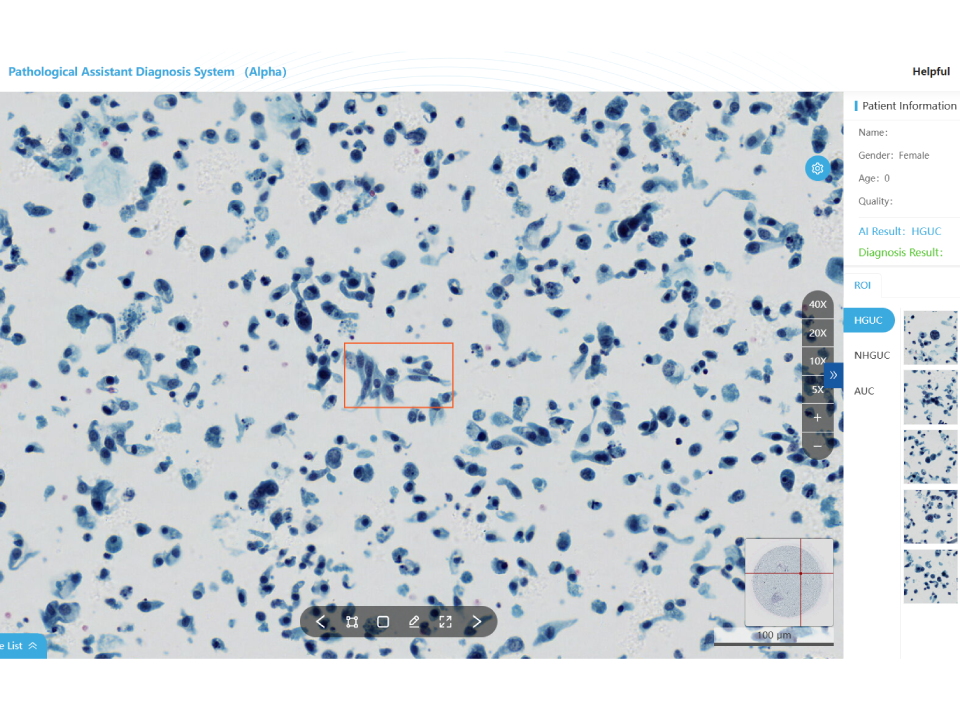

Urine Cytology Assistant Diagnostic Module

Automatic recognition of high-grade uroepithelial cancer cells Diagnostic report based on "The Evolution of the Paris System(TPS)" Validated by multi-center clinical trials: Sensitivity≥95%,Specificity≥93% Whole slide analysis to reduce missed defections Increase the positive detection rate

Urine Cytology Assistant Diagnostic Module

- Automatic recognition of high-grade uroepithelial cancer cells

- Diagnostic report based on “The Evolution of the Paris System(TPS)”

- Validated by multi-center clinical trials: Sensitivity≥95%,Specificity≥93%

- Whole slide analysis to reduce missed defections

- Increase the positive detection rate